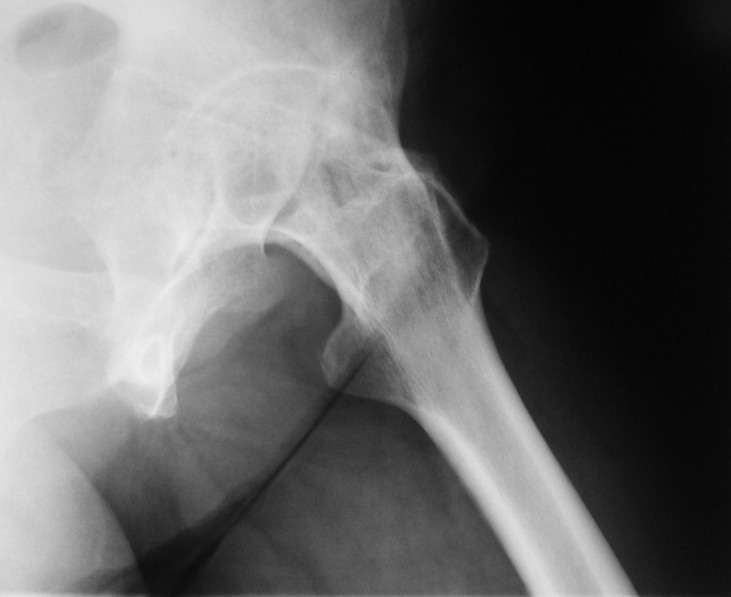

При обследовании выявлен анкилоз тазобедренного сустава в приведении.

Видимо, в период пребывания в тяжелом состоянии появились

гетеротопические оссификаты. За исключением того, что осталась одна

Корсет и анальгетики вряд ли решение. Первый вариант - удаление

оссификатов и эндпротезирование, второй - корригирующая остеотомия в

проксимальном отделе с устранением порочного положения.